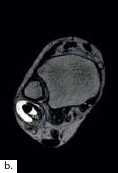

Die Diagnose einer OSG-Distorsion, die später als Grundlage einer adäquaten Therapie dient, ergibt sich aus der Kombination von Befunden verschiedener diagnostischer Ebenen (Anamnese, klinische Untersuchung, bildgebende Diagnostik). Die Erstdiagnostik nach dem Unfall beinhaltet Röntgenaufnahmen des OSG in zwei Ebenen. Im Verlauf und bei persistierenden Beschwerden können MRT- (Abb. 2) oder CT-Aufnahmen angefertigt werden, um Begleitverletzungen wie osteochondrale Frakturen (Abb. 3a), Syndesmosenverletzung oder Peronealsehnenaffektion (Abb. 3b) nachzuweisen.